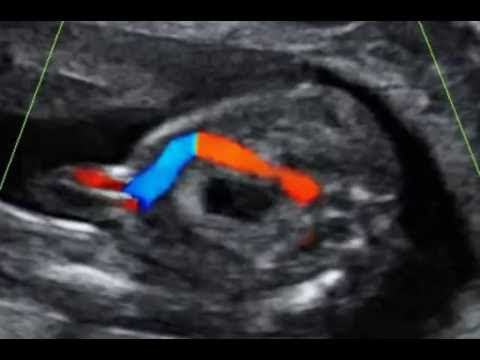

Umbilical Cord 1 Vein And 1 Artery

October 26, 2017 Add Comment

Video Umbilical Cord 1 Vein And 1 Artery

VIDEO : should i be worried that my baby's umbilical cord has only 1 artery instead of 2? - the question, what to do with an incidental finding of singlethe question, what to do with an incidental finding of singleumbilical arteryat the t ...

VIDEO : i have a single umbilical artery. should i be concerned? - thetheumbilical cordtypically contains twothetheumbilical cordtypically contains twoarteriesandthetheumbilical cordtypically contains twothetheumbilical cordtypically cont ...

2 Umbilical Cord Blood Vessels

October 26, 2017 2 Comments

Video 2 Umbilical Cord Blood Vessels

VIDEO : 21 week ultrasound || two vessel umbilical cord abnormality found - we had our 21 week ultrasound on monday and unfortunately they found an abnormality in thewe had our 21 week ultrasound on monday and unfortunately they found an ...

VIDEO : 2 vessel umbilical cord, 33 weeks pregnant - my first video ever, excuse the chokiness and my words seem to be all over the place :/ oh my. ...